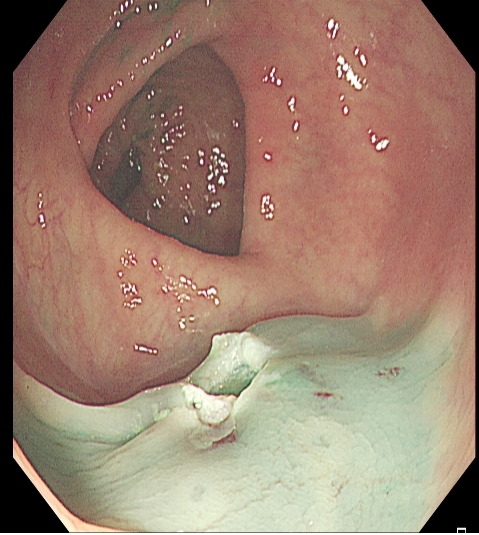

对于大型Ⅰp病变,除以上注意事项外,应采用热圈套方式切除,切除前应于蒂根部充分黏膜下注射(经内镜注射针将2~10 mLl万单位的肾上腺素+亚甲蓝+生理盐水混合液注射于黏膜下,边退针边注射),致使蒂部充分隆起,易于切除(图 3),切除过程中病变应避免接触肠壁,以免形成闭合回路,灼伤肠壁。